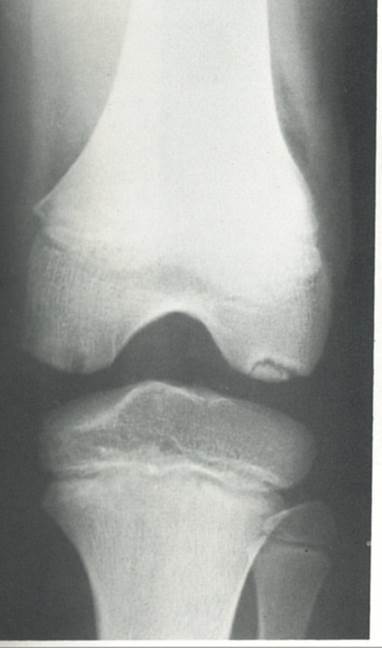

Legg-calve-perthes disease

Four stages of LCPD

TX of LCPD